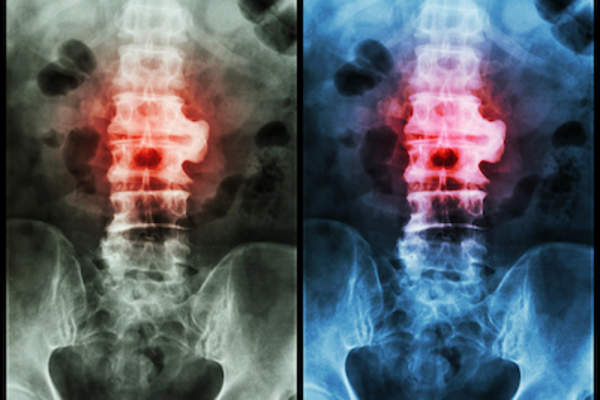

强直性脊柱炎

强直性脊柱炎是一种来源不明的无法治愈的炎症性疾病,通常影响脊柱和下背部。因为强直性脊柱炎是进行性和全身性的,它还可以影响身体的许多不同部位,包括关节和器官。这里有11种可能的并发症。